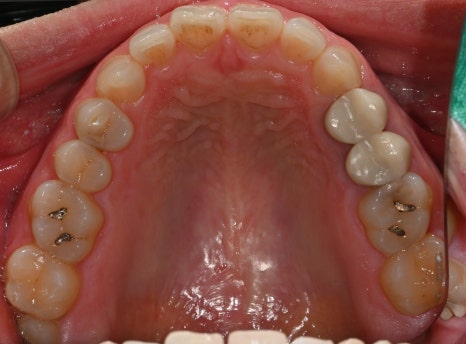

Second photo: Upper molar photo taken at the initial visit. The caries area and the broken tooth condition are visible.